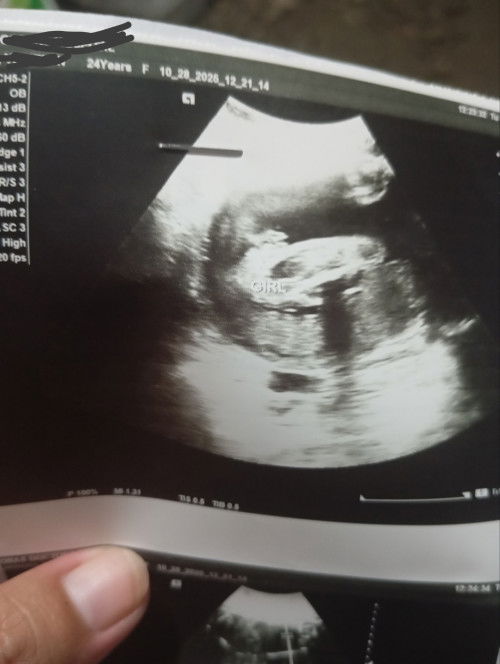

Legit kaya Na baby girl to?

Hello 6 months pregnant here 👋 Panganay ko boy, hoping na sana baby girl na to🥺💖